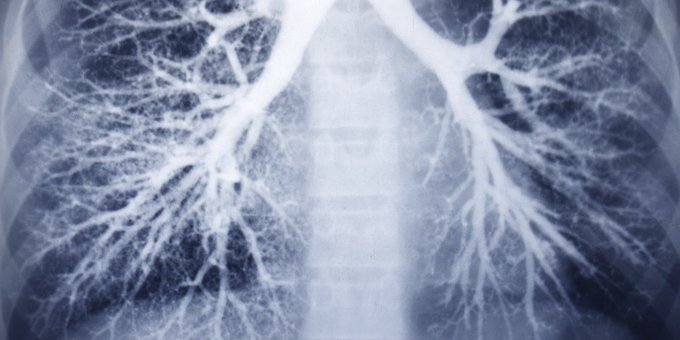

La neumonía es una infección de uno o los dos pulmones. Muchos gérmenes, como bacterias, virus u hongos, pueden causarla. ¿Cuáles son las personas con mayor riesgo? Entérate aquí ow.ly/eY8l50A26sc